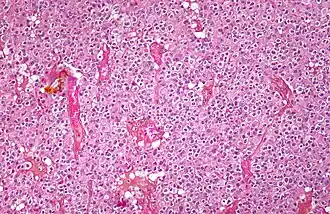

Micrograph of an oligodendroglioma showing the characteristic branching, small, chicken wire-like blood vessels and fried egg-like cells, with clear cytoplasm and well-defined cell borders. H&E stain. | |

Oligodendrogliomas cannot currently be differentiated from other brain lesions solely by their clinical or radiographic appearance. As such, a brain biopsy is the only method of definitive diagnosis. Oligodendrogliomas recapitulate the appearance of the normal resident oligodendroglia of the brain. (Their name derives from the Greek roots 'oligo' meaning "few" and 'dendro' meaning "trees".) They are generally composed of cells with small to slightly enlarged round nuclei with dark, compact nuclei and a small amount of eosinophilic cytoplasm. They are often referred to as "fried egg" cells due to their histologic appearance (though, the perinuclear halo on permanent sections is an artifact of tissue drying; fresh tissue lacks this characteristic "fried egg" appearance). They appear as a monotonous population of mildly enlarged round cells infiltrating normal brain parenchyma and producing vague nodules. Although the tumor may appear to be vaguely circumscribed, it is by definition a diffusely infiltrating tumor.[6]

Classically they tend to have a vasculature of finely branching capillaries that may take on a "chicken wire" appearance. When invading grey matter structures such as cortex, the neoplastic oligodendrocytes tend to cluster around neurons exhibiting a phenomenon referred to as "perineuronal satellitosis". Oligodendrogliomas may invade preferentially around vessels or under the pial surface of the brain.[6]